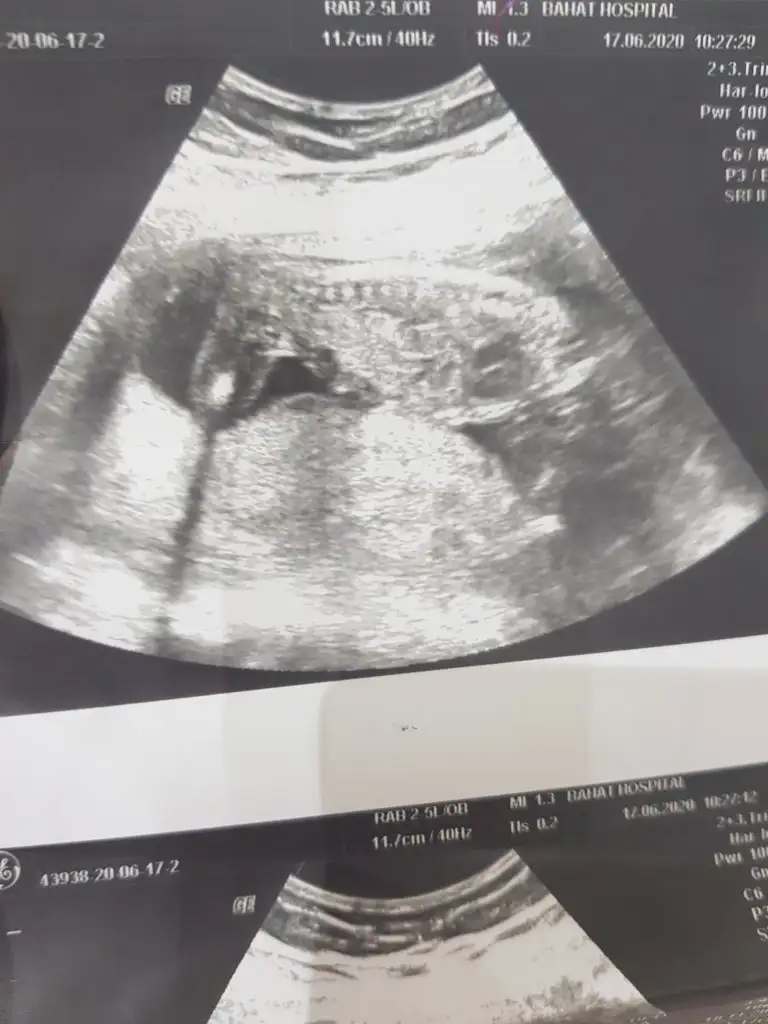

Bunlar net değilBi de bu resimler var.

ÖgrendinizmiEvet net bulamadım en net resmi bu doktor net çekmemiş aslında 12 haftalık teşekkür ederim

Üçlü taramada büyük ihtimalle kız olduğu söylendiNet degil usg tek tek çekermisiniz usgler yada başka usg olursa paylaşın 12-13 haftalarda olabilir şimdilik eminde değilim kız gibi gibi emin değilim tekrar usg paylaşın